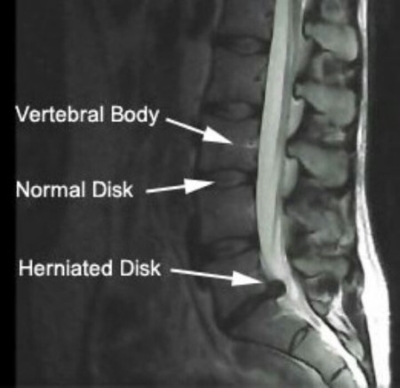

椎间盘的问题:椎间盘是位于脊椎骨之间的软骨垫,当其脱出、膨出或突出时,可能会压迫神经根或脊髓,引发腰痛,椎间盘突出症是膨出、突出、脱出这样的一个过程。

诊断:基于患者的症状、体格检查和影像学结果,张先生被诊断为腰椎间盘突出症。